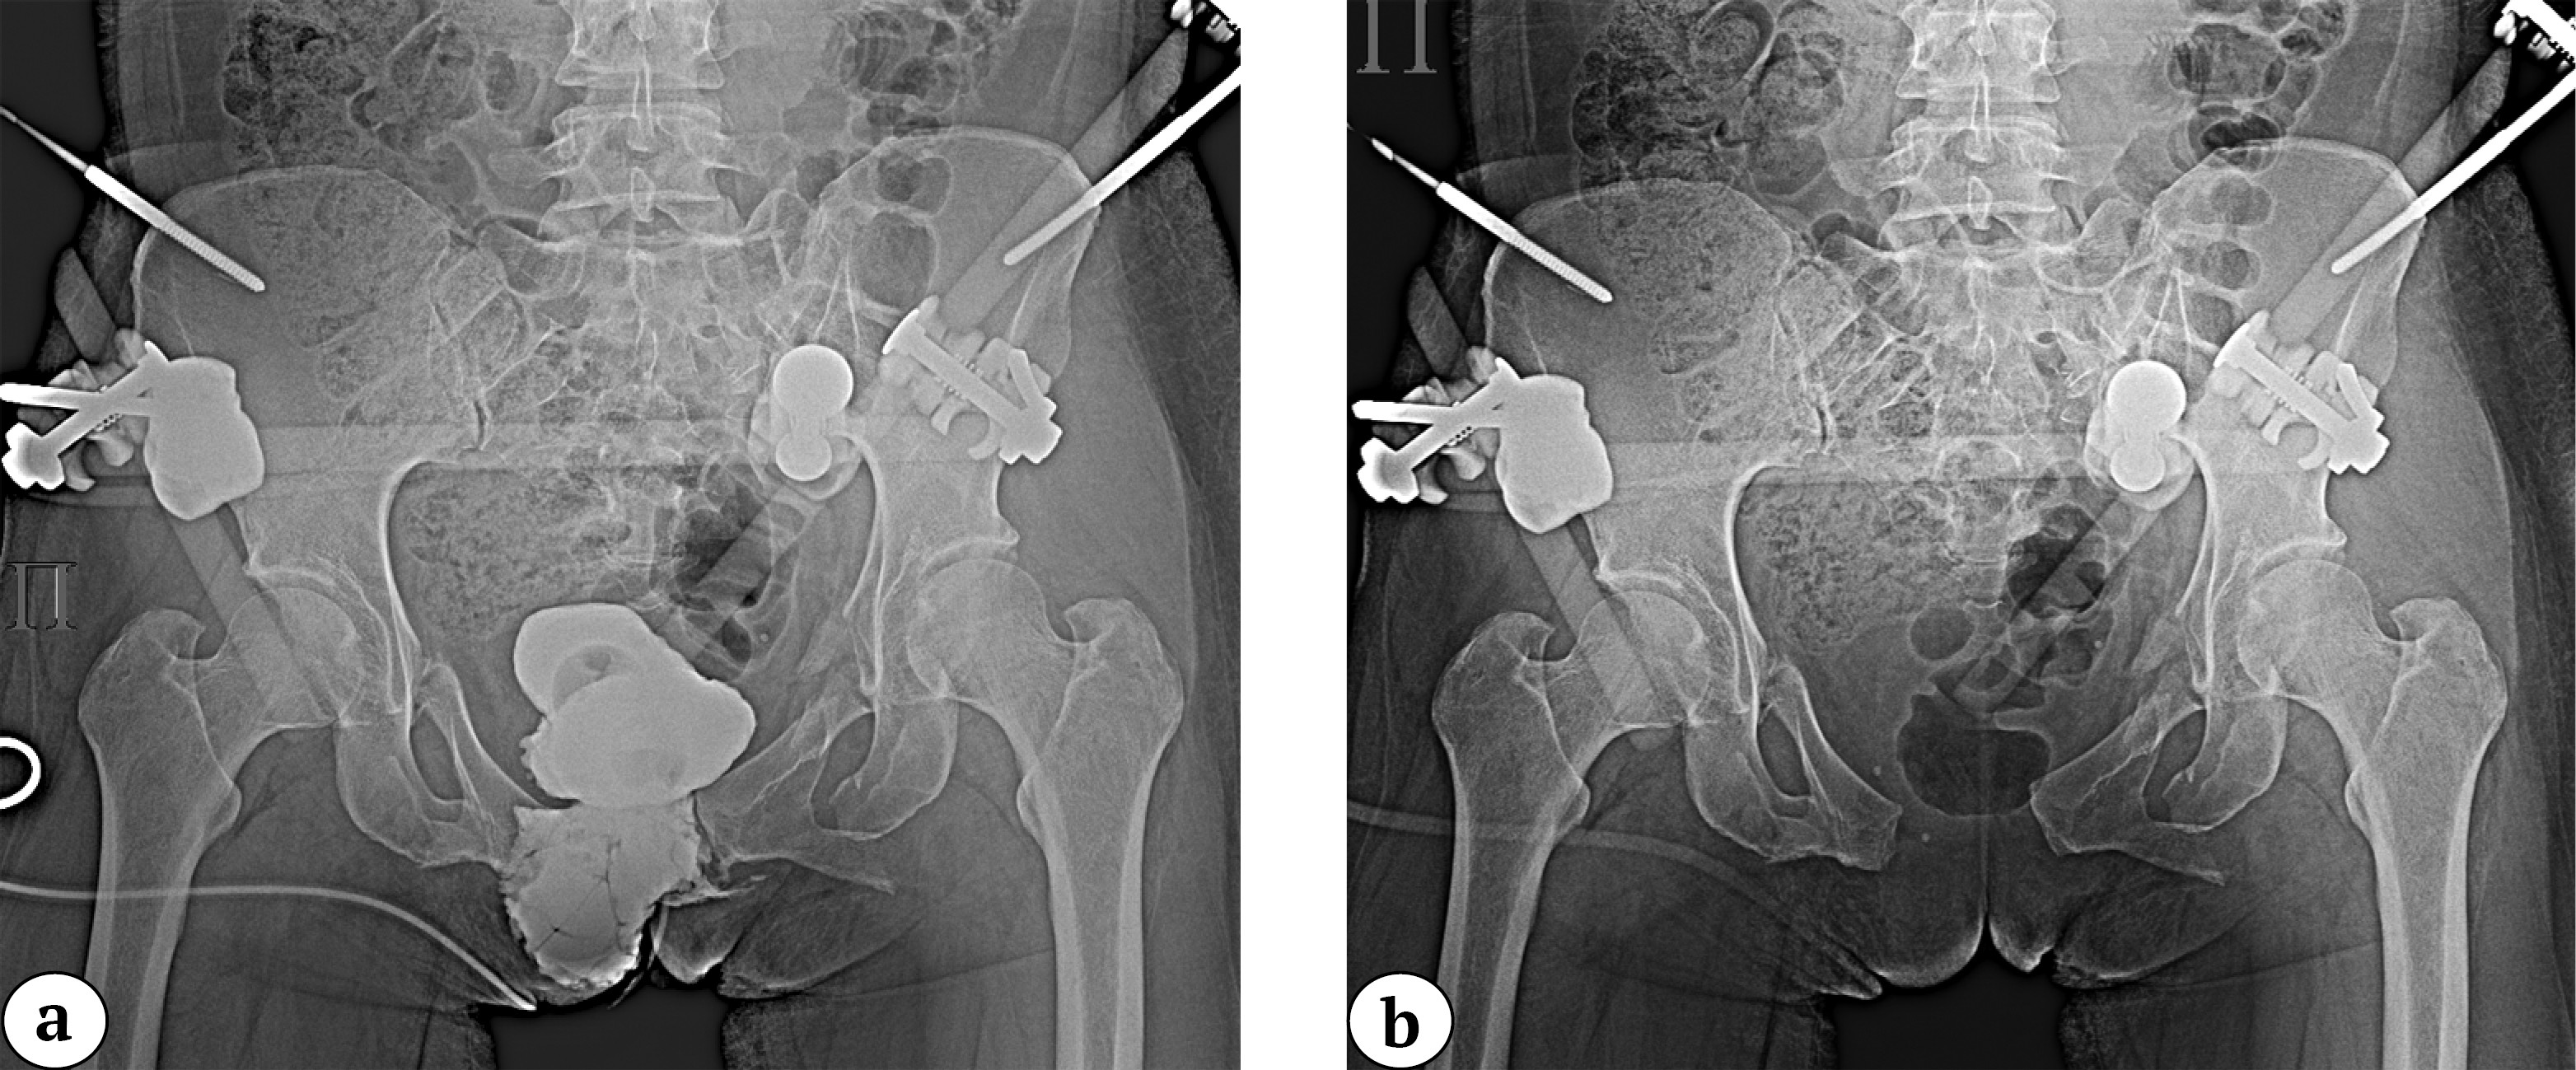

The Pfannenstiel approach allows simulta-neous osteosynthesis of bilateral pubic rami fractures with concomitant pubic symphysis disruption, even in the presence of various anterior abdominal wall defects. For example, this technique can be applied in patients with a colostomy or concomitant bladder rupture (Figure 7).

Figure 7. Pelvic X-ray in the anteroposterior view: symphyseal disruption with significant diastasis and fractures of both pubic bones (a); cystogram showing extravasation of contrast beyond the bladder contour (b)

It is important to note that the presented method of anterior pelvic ring stabilization is usually part of a comprehensive surgical approach. In cases associated with posterior ring instability, it should be combined with appropriate fixation techniques, chosen indi-vidually based on the complete diagnostic assessment. In our practice, cannulated 6.5-mm screws were typically used (Figure 8).

Figure 8. Postoperative X-ray: anterior fixation with the nail-plate system and sacral fixation with cannulated screws in S1 and S2 (a); 2D CT reconstruction of the pelvis postoperatively confirming restoration of the pelvic ring anatomy with fixation of the sacrum, pubic bones, and symphysis (b)